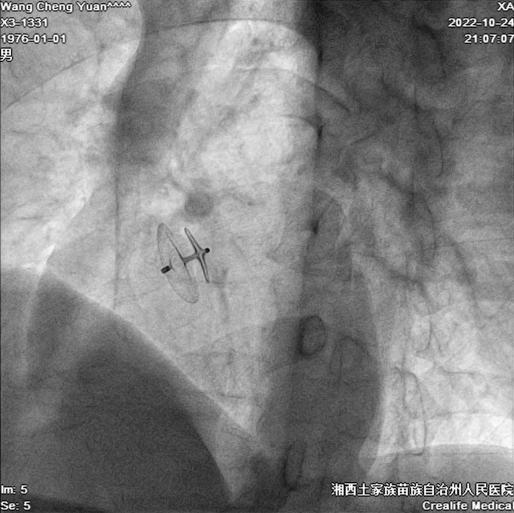

近日,湘西州人民医院心血管内三科成功为一名卵圆孔未闭患者实施了卵圆孔介入封堵术,帮助其解决了困扰多年的头痛烦恼,患者已于10月26日康复出院。

10月24日晚,在彭林林指导下,邓策成功为王先生实施了卵圆孔介入封堵术。手术过程顺利,全程耗时约30分钟,术后仅在患者右侧大腿根部留有针眼大小的穿刺伤口,术后8小时即可下床正常活动,术后患者头疼症状消失。